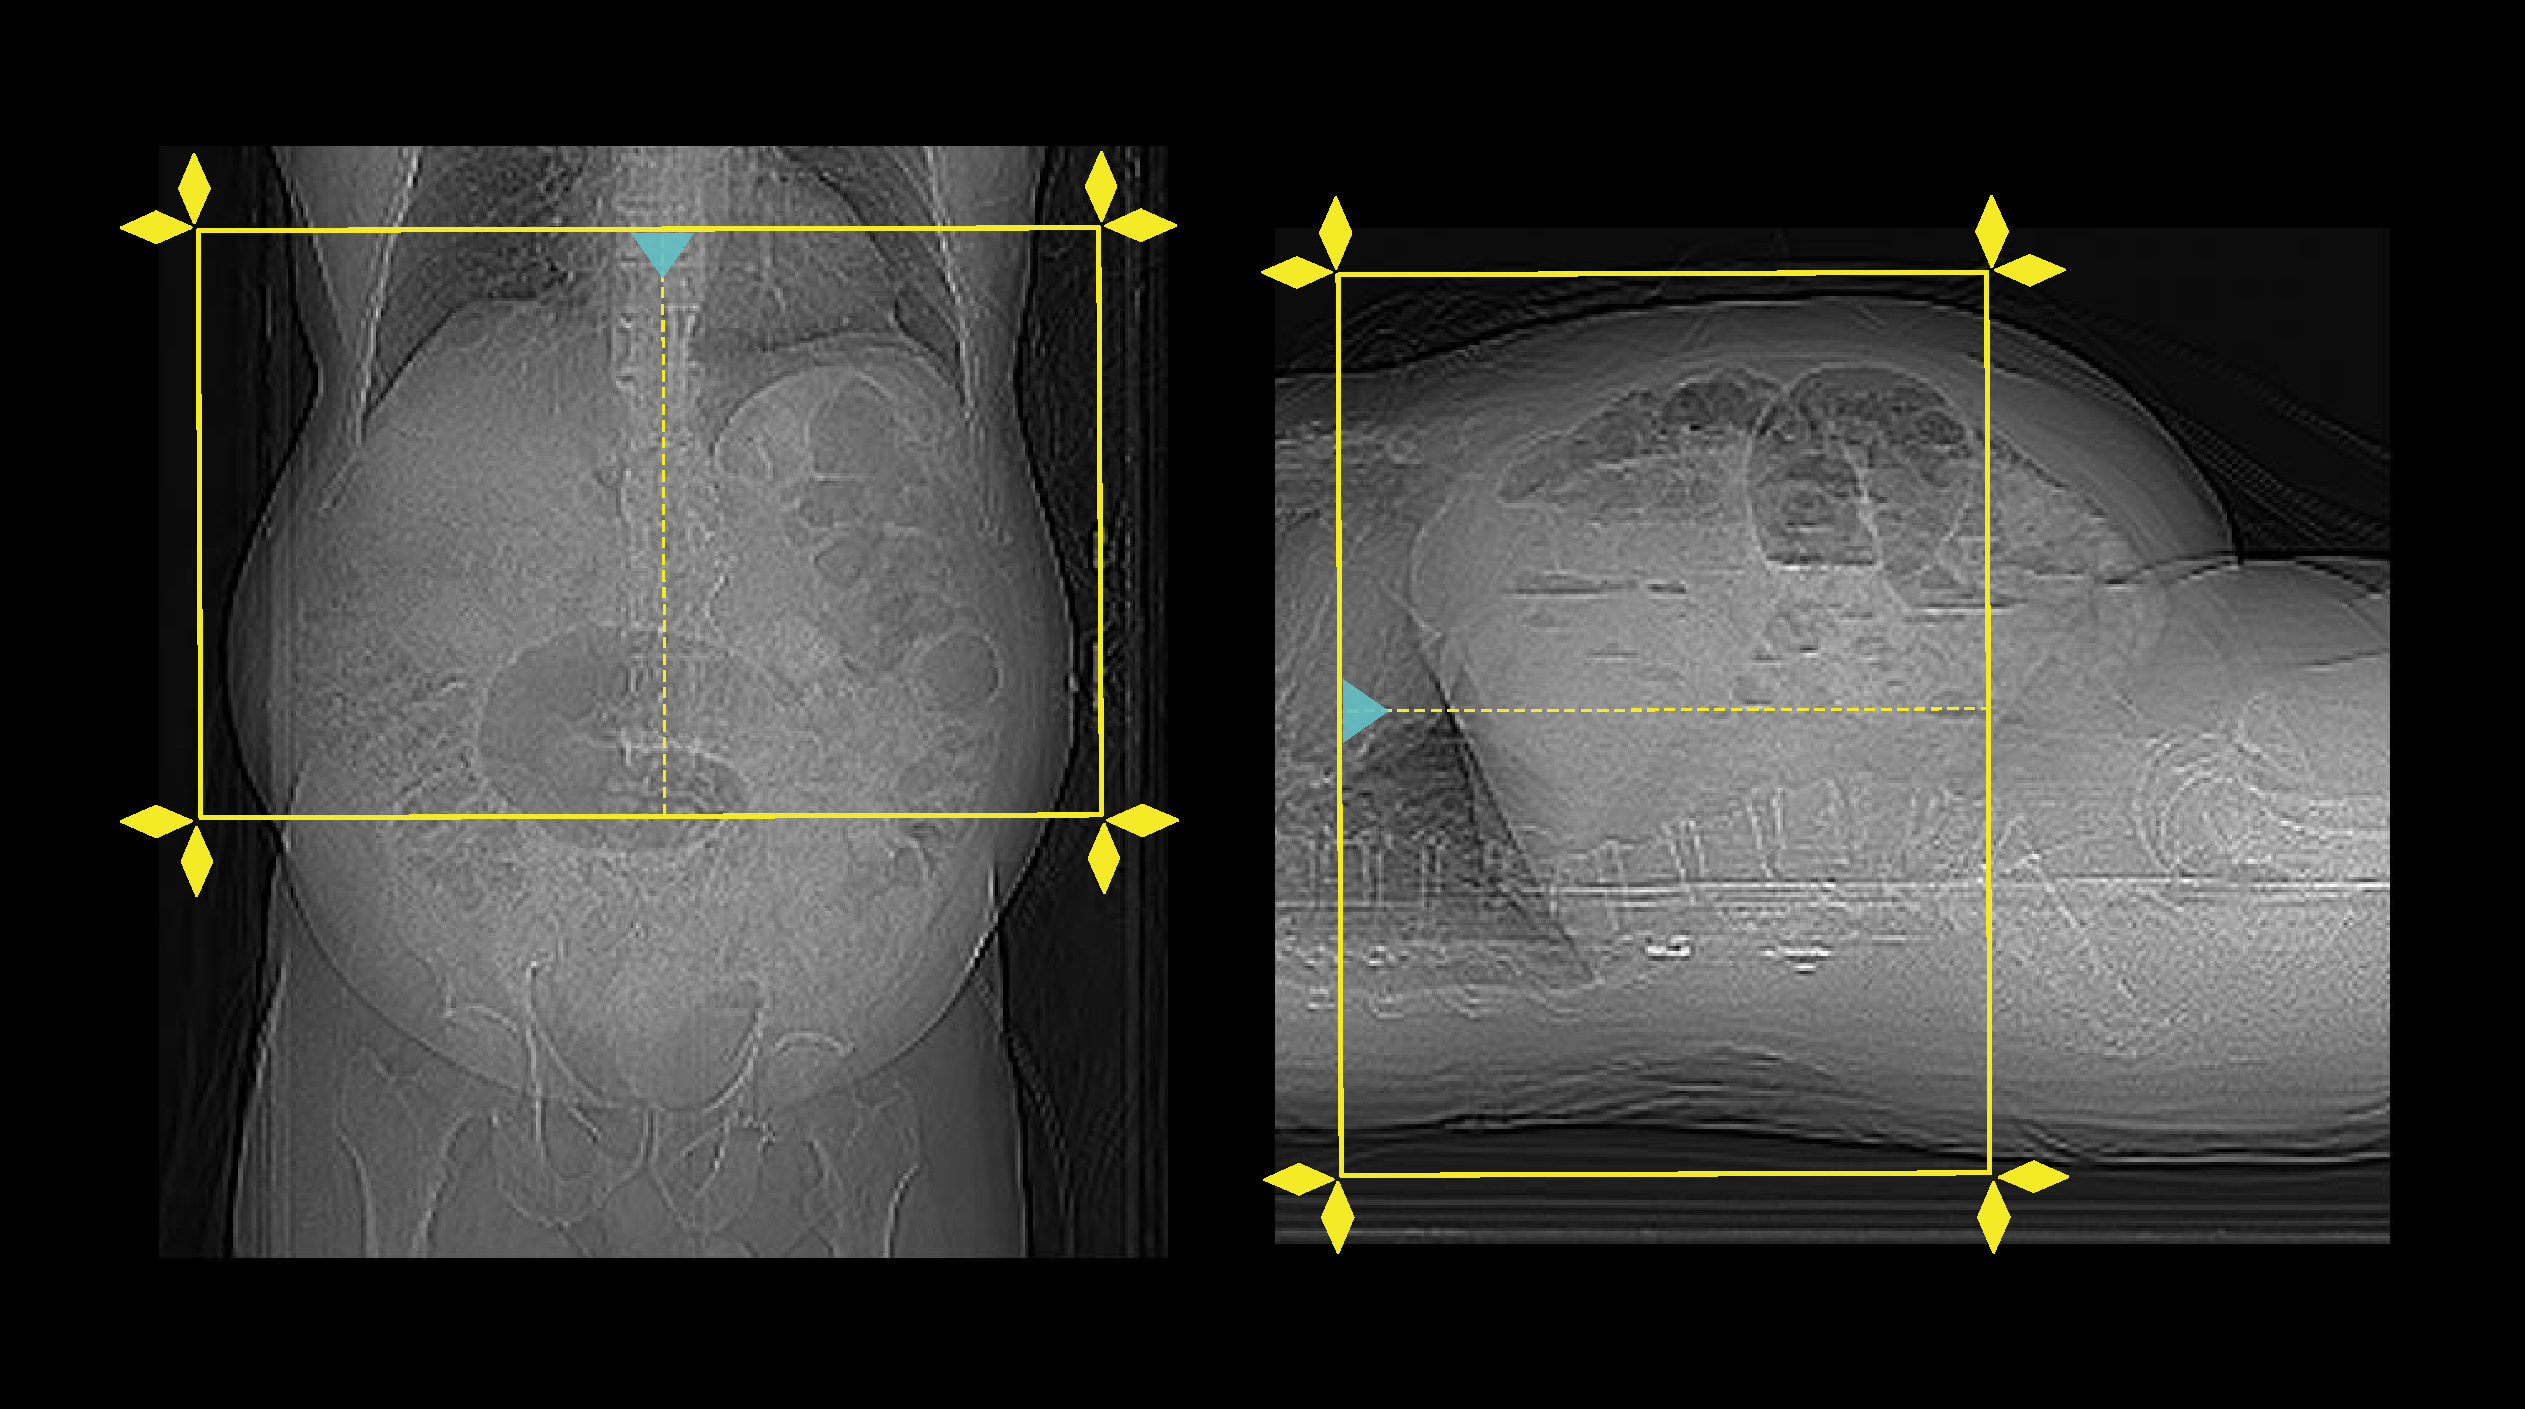

- Position the patient in feet first and supine.

- Center the scanning area in the scanner iso-center [6].

- Place both hands above the head.

- If abdomen or upper abdomen, plan the scan slab from the dome of the diagram to the upper margin of the sacroiliac joints. However, lower end point of the scan can be extended to the pelvic region according to diagnostic needs.

- If abdomen and pelvis, plan the scan slab from the dome of the diagram to a level just below the ischial tuberosities.